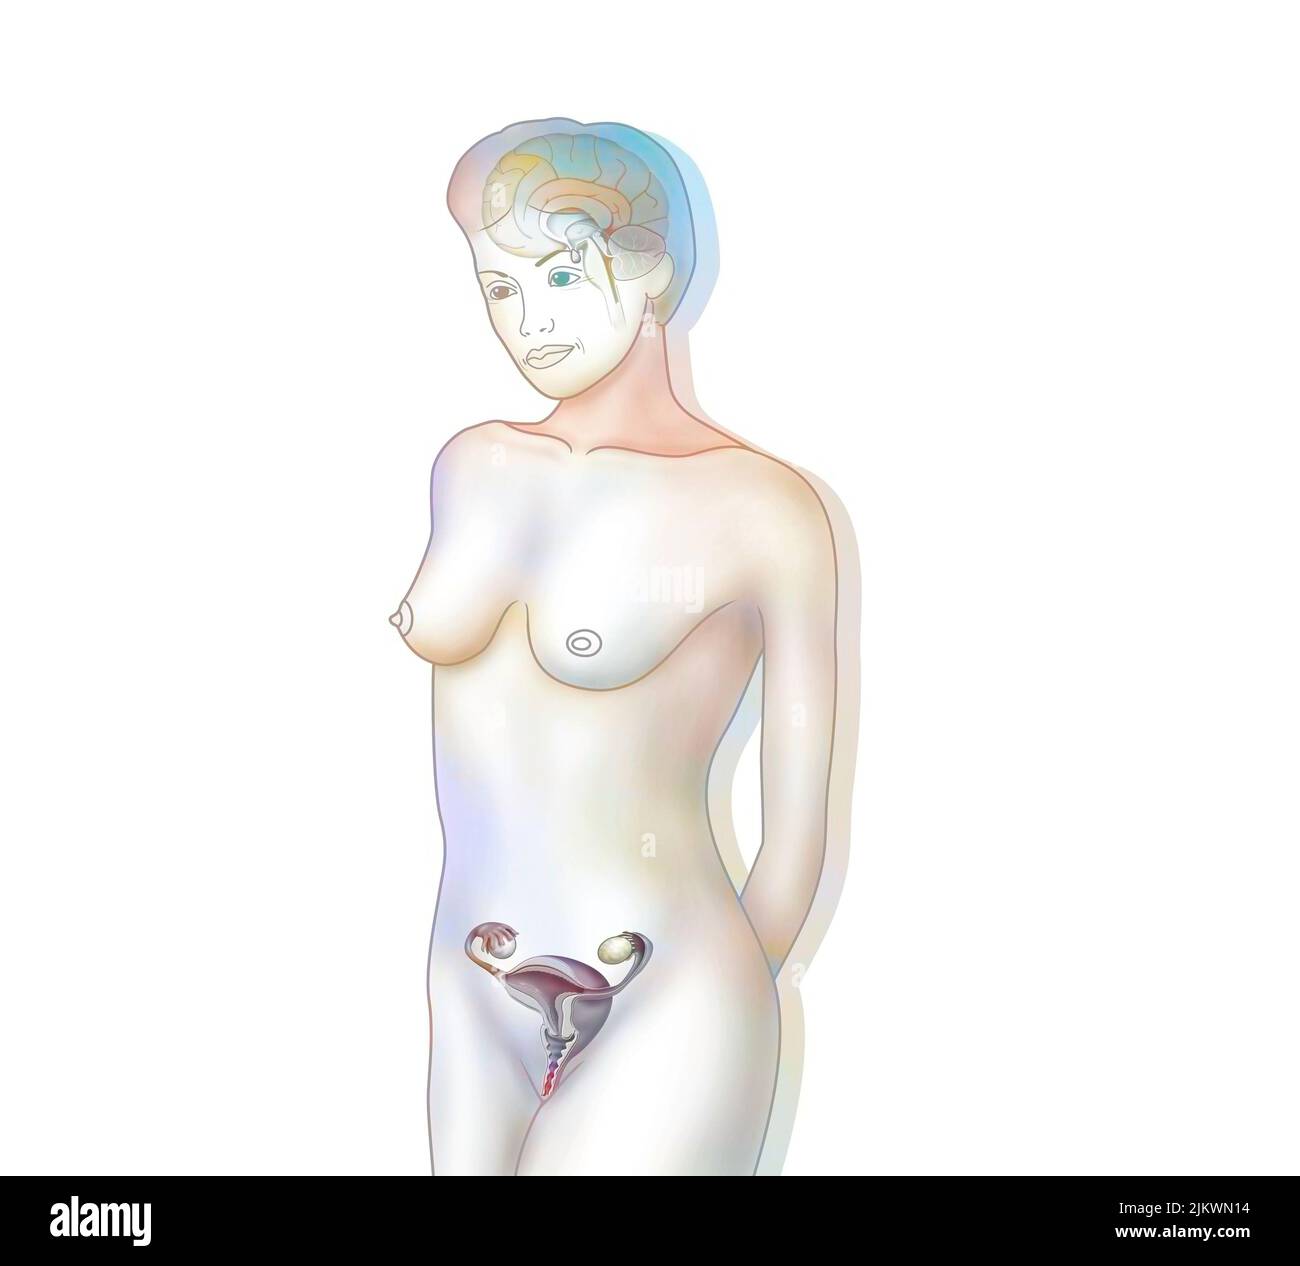

RF2JKWRM1–Vue antérieure des organes génitaux féminins avec vagin, utérus, trompes de Fallope, ovaires.